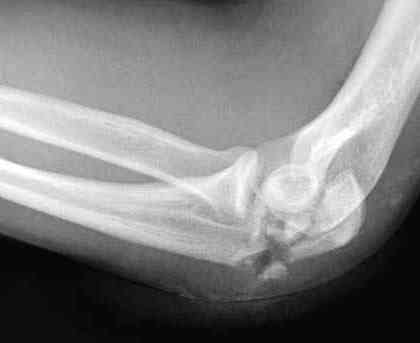

Здесь выставлены несколько случаев и варианты фиксации локтевого

отростка, некоторые в комбинации с другими переломами.

Вложение не в текстовом формате было извлечено…

Имя     : 2 olecranon injury AP 1.jpg

Тип     : image/jpeg

Размер  : 17944 байтов

Описание: отсутствует

Url     : http://weborto.net:8080/pipermail/ortho/attachments/20071121/9a993135/attachment-0007.jpg